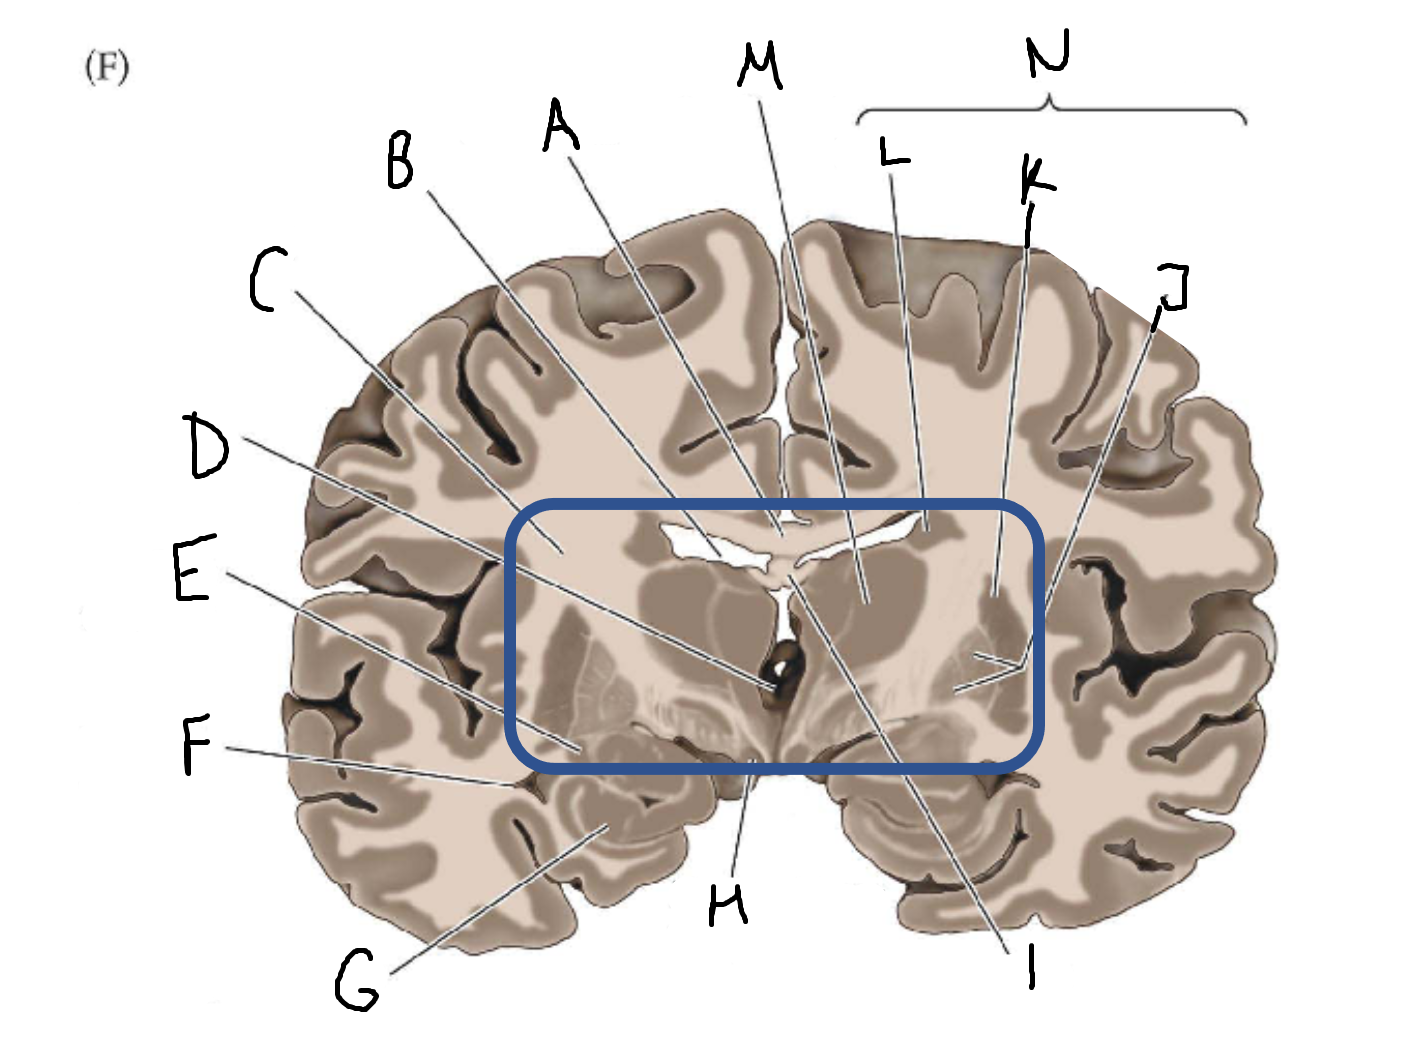

A

corpus callosum

B

lateral ventricle

C

internal capsule

D

third ventricle

E

tail of caudate nucleus

F

lateral ventricle

G

hippocampus

H

mammillary body

I

fornix

J

globus pallidus

K

putamen

L

caudate

M

thalamus

N

basal ganglia